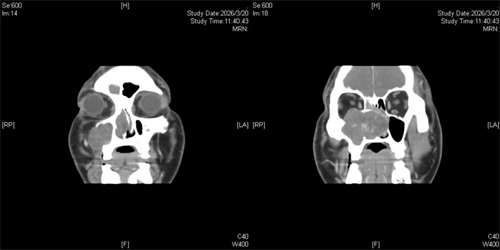

鼻窦CT检查结果触目惊心:患者鼻腔鼻窦内肿瘤约7.0厘米×5.0厘米(约鹅蛋大小),呈膨胀性生长,已侵犯颌面部皮下、眶内,破坏上颌窦骨质,甚至侵及对侧鼻腔,病情十分凶险。